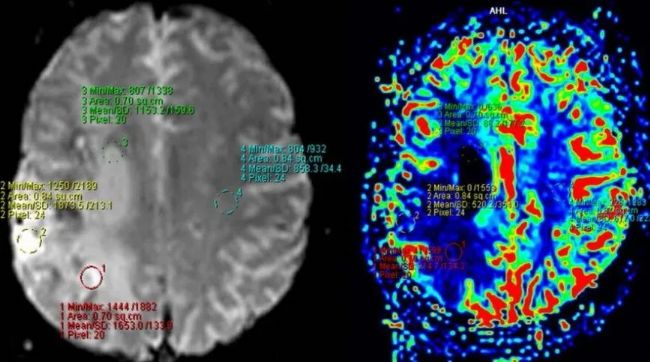

圖1:腦灌注MRI顯示右側(cè)大腦中動(dòng)脈(MCA)區(qū)域的灌注減少。圖片來自Feres Chaddad博士教授。